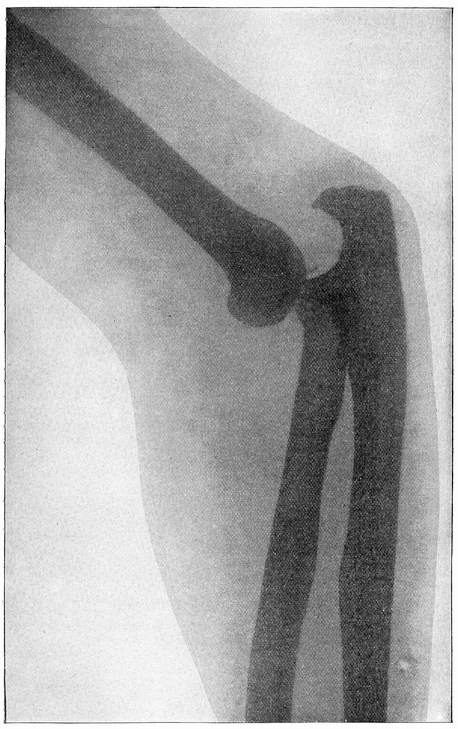

| X-Ray Picture of a Dislocated Elbow. Full page | 629xviii |